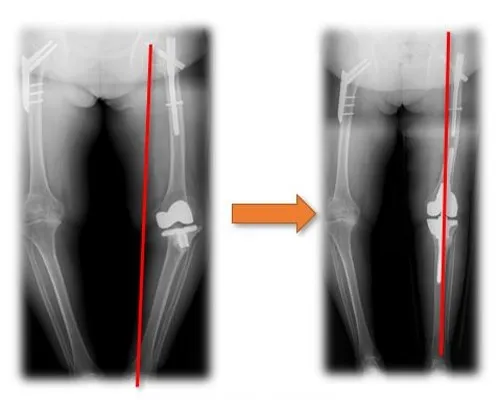

Total hip replacement for osteoarthritis secondary to hip dysplasia

Through three-dimensional reconstruction of medical CT data, porous implants with bionic trabecular structures such as joint, spine, craniofacial bone and extremities can be manufactured by using three-dimensional printing techniques like electron beam melting, selective laser melting and selective laser sintering. The factors such as porosity, pore size and pore reinforcement can be adjusted for individuals, which is more conducive to bone growth and is better in clinical effect.

Absolutely. These are specifically designed for total hip replacement in cases of osteoarthritis secondary to hip dysplasia.

Yes, we provide three-dimensional reconstruction from medical CT data to create bionic trabecular structures tailored to each patient.